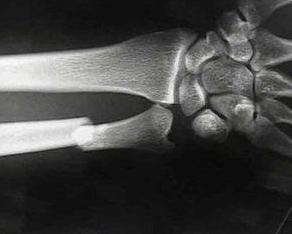

♥尺骨干骨折

多见于外力突然袭击,患者举手遮挡头面部时被棍棒直接打击所致。因多发生在路遇强人情况下,故又名夜盗(杖)骨折。此骨折线多呈横形或带有三角形骨块。尺骨干单骨折极少见。